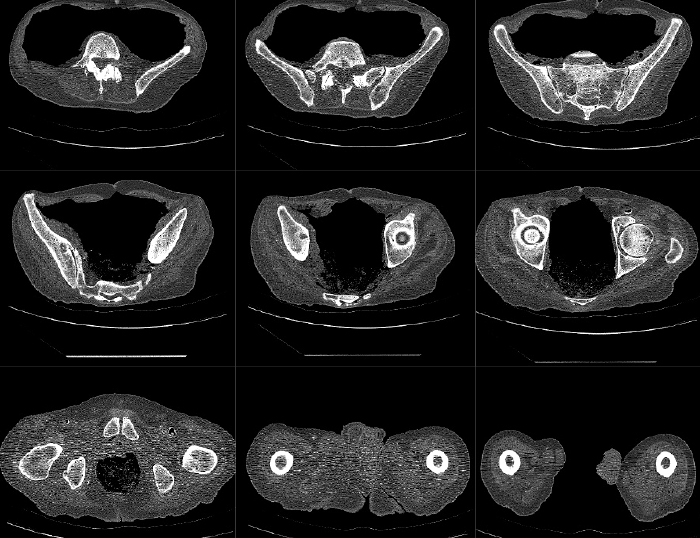

Mako Robotic-Arm Assisted Technology provides you with a personalized surgical plan based on your unique anatomy. First, a CT scan of the diseased joint is taken. This CT scan is uploaded into the Mako System software, where a 3D model of your hip is created. This 3D model is used to pre-plan and assist your surgeon in performing your total hip replacement.